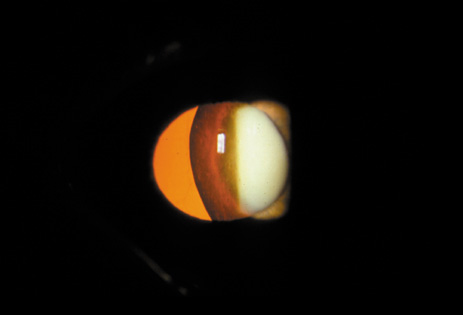

The PSC is the least prevalent subtype in most population-based studies.18 These cataracts often occur in combination with nuclear or cortical cataracts in the later stages. They are easily noticed on retroillumination because they are usually located centrally, and may interfere with funduscopy (Fig. 12). In early stages, patients usually complain of subjective symptoms such as glare disability32 and difficulty focusing on near objects. This is because when the pupil constricts during accommodation, the light entering the eye becomes concentrated centrally, where the PSC is also located. This causes light scattering and interferes with the ability of the eye to focus an image on the macula. In addition, these opacities lie at or near the nodal point of the eye, further interfering with focusing of the image on the macula.

Fig. 12. PSC. Note the central location, which gives rise to severe glare disability.

One can examine this type of cataract with direct illumination, using the narrow and broad beams of the slit-lamp to show the characteristic granular inner surface immediately in front of the posterior capsule (Fig. 13). The problem with this technique, however, is that patients may not tolerate any prolonged direct illumination because of the glare. Retroillumination is therefore more useful for revealing the outline of the opacity, since it is usually seen as an “island” in the center of the posterior capsule, which is further highlighted by the shadow cast by the opacities.33 However, in the early stages of this type of cataract, the dust-like particles that might be noticeable in the central posterior subcapsular area with direct illumination disappear or are difficult to see with retroillumination (Fig. 14). Eventually this “dusting” becomes dense enough to cast a shadow and thus appear on retroillumination. The smooth orange background of the fundus helps to highlight the rough, irregular pseudopodia-like edges of the central opacity. In advanced stages, the PSC may become a thick, calcified plaque (Fig. 15). During surgery, excessively vigorous scraping or vacuuming of the calcified opacity can lead to rupture of the posterior capsule. Usually, small remnants that are left behind after surgery are reabsorbed and do not interfere with vision; otherwise, they are easily treated with a neodymium : yttrium (Nd:YAG) aluminum garnet laser. Pathologic evidence suggests that most PSCs result from the migration of bow region cells into the potential space (along with accumulated cellular debris) between the posterior capsule and the cortex.34–36

Fig. 13. Direct slit-lamp illumination of a PSC, showing an irregular granular surface in front of the posterior capsule.